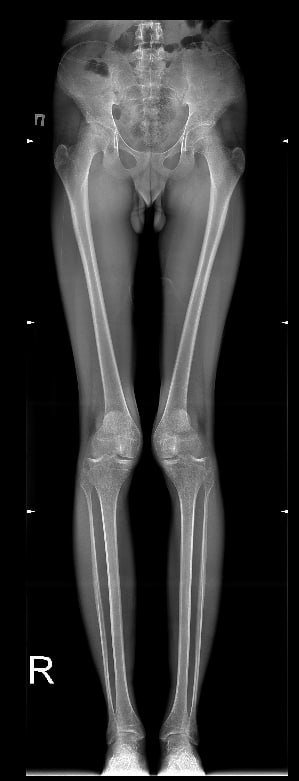

У меня такая же хуйня, но куда хуже, с рождения двухсторонняя дисплазия, в лет 11 началось проявление вальгусной деформации ног, спустя год стали вылетать надколенники (чашечки). С каждым годом это все ухудшалось и ухудшалось. Родители особо не торопились меня отводить к врачам, по этому к 14 я утратил способность нормально ходить (вечный страх что вот вот вылетит колено и я упаду) бегать я вовсе не могу, потому что надколенники сместились латерально кверху, по этому стабильность моих ног начинает качать уже от обычного ветра. Из за этого я не смог подписать контракт в 18 как и хотел, но начал процесс какого либо контакта с врачами и поиска решения проблемы без мам и пап. Сам выбивал справки и направления на бесплатные обследования. Спустя 4 месяцев сбора кучи обследования, пару рентгенов, пару мрт и одного торсиального кт. Мой хирург который взял меня под свое крыло, увидел во мне необычайно удивительный случай. Моментально уехал в Москву, там на какой то крутой конференции, он показал мои результаты обследований и видео подвижности моих ног другим врачам и как он передал, там все ахуели. Предложил мне относительно сложную операцию, типичная остеотомия, только пилить будут в двух местах бедро, в трёх большеберцовую кость и резекцию икры для предотвращения спазма нервов ну и замена связок на надколеннике. В итоге, мне остаётся букалаьно две недели до госпитализация и две недели и один день до операции. Я очень волнуюсь, потому что я забыл что уже такое бегать, что такое прыгать и ходить без страха вывихнуть колено.

IMG202507271253[...].jpg 97Кб, 577x1280

IMG202507271253[...].jpg 228Кб, 1280x960

IMG202507271253[...].jpg 195Кб, 960x1280

IMG202507271253[...].jpg 182Кб, 960x1280

IMG202507271253[...].jpg 183Кб, 1217x959

IMG202507271253[...].jpg 199Кб, 1224x892

IMG202410312014[...].jpg 25Кб, 299x781

IMG202507271253[...].jpg 126Кб, 1138x788